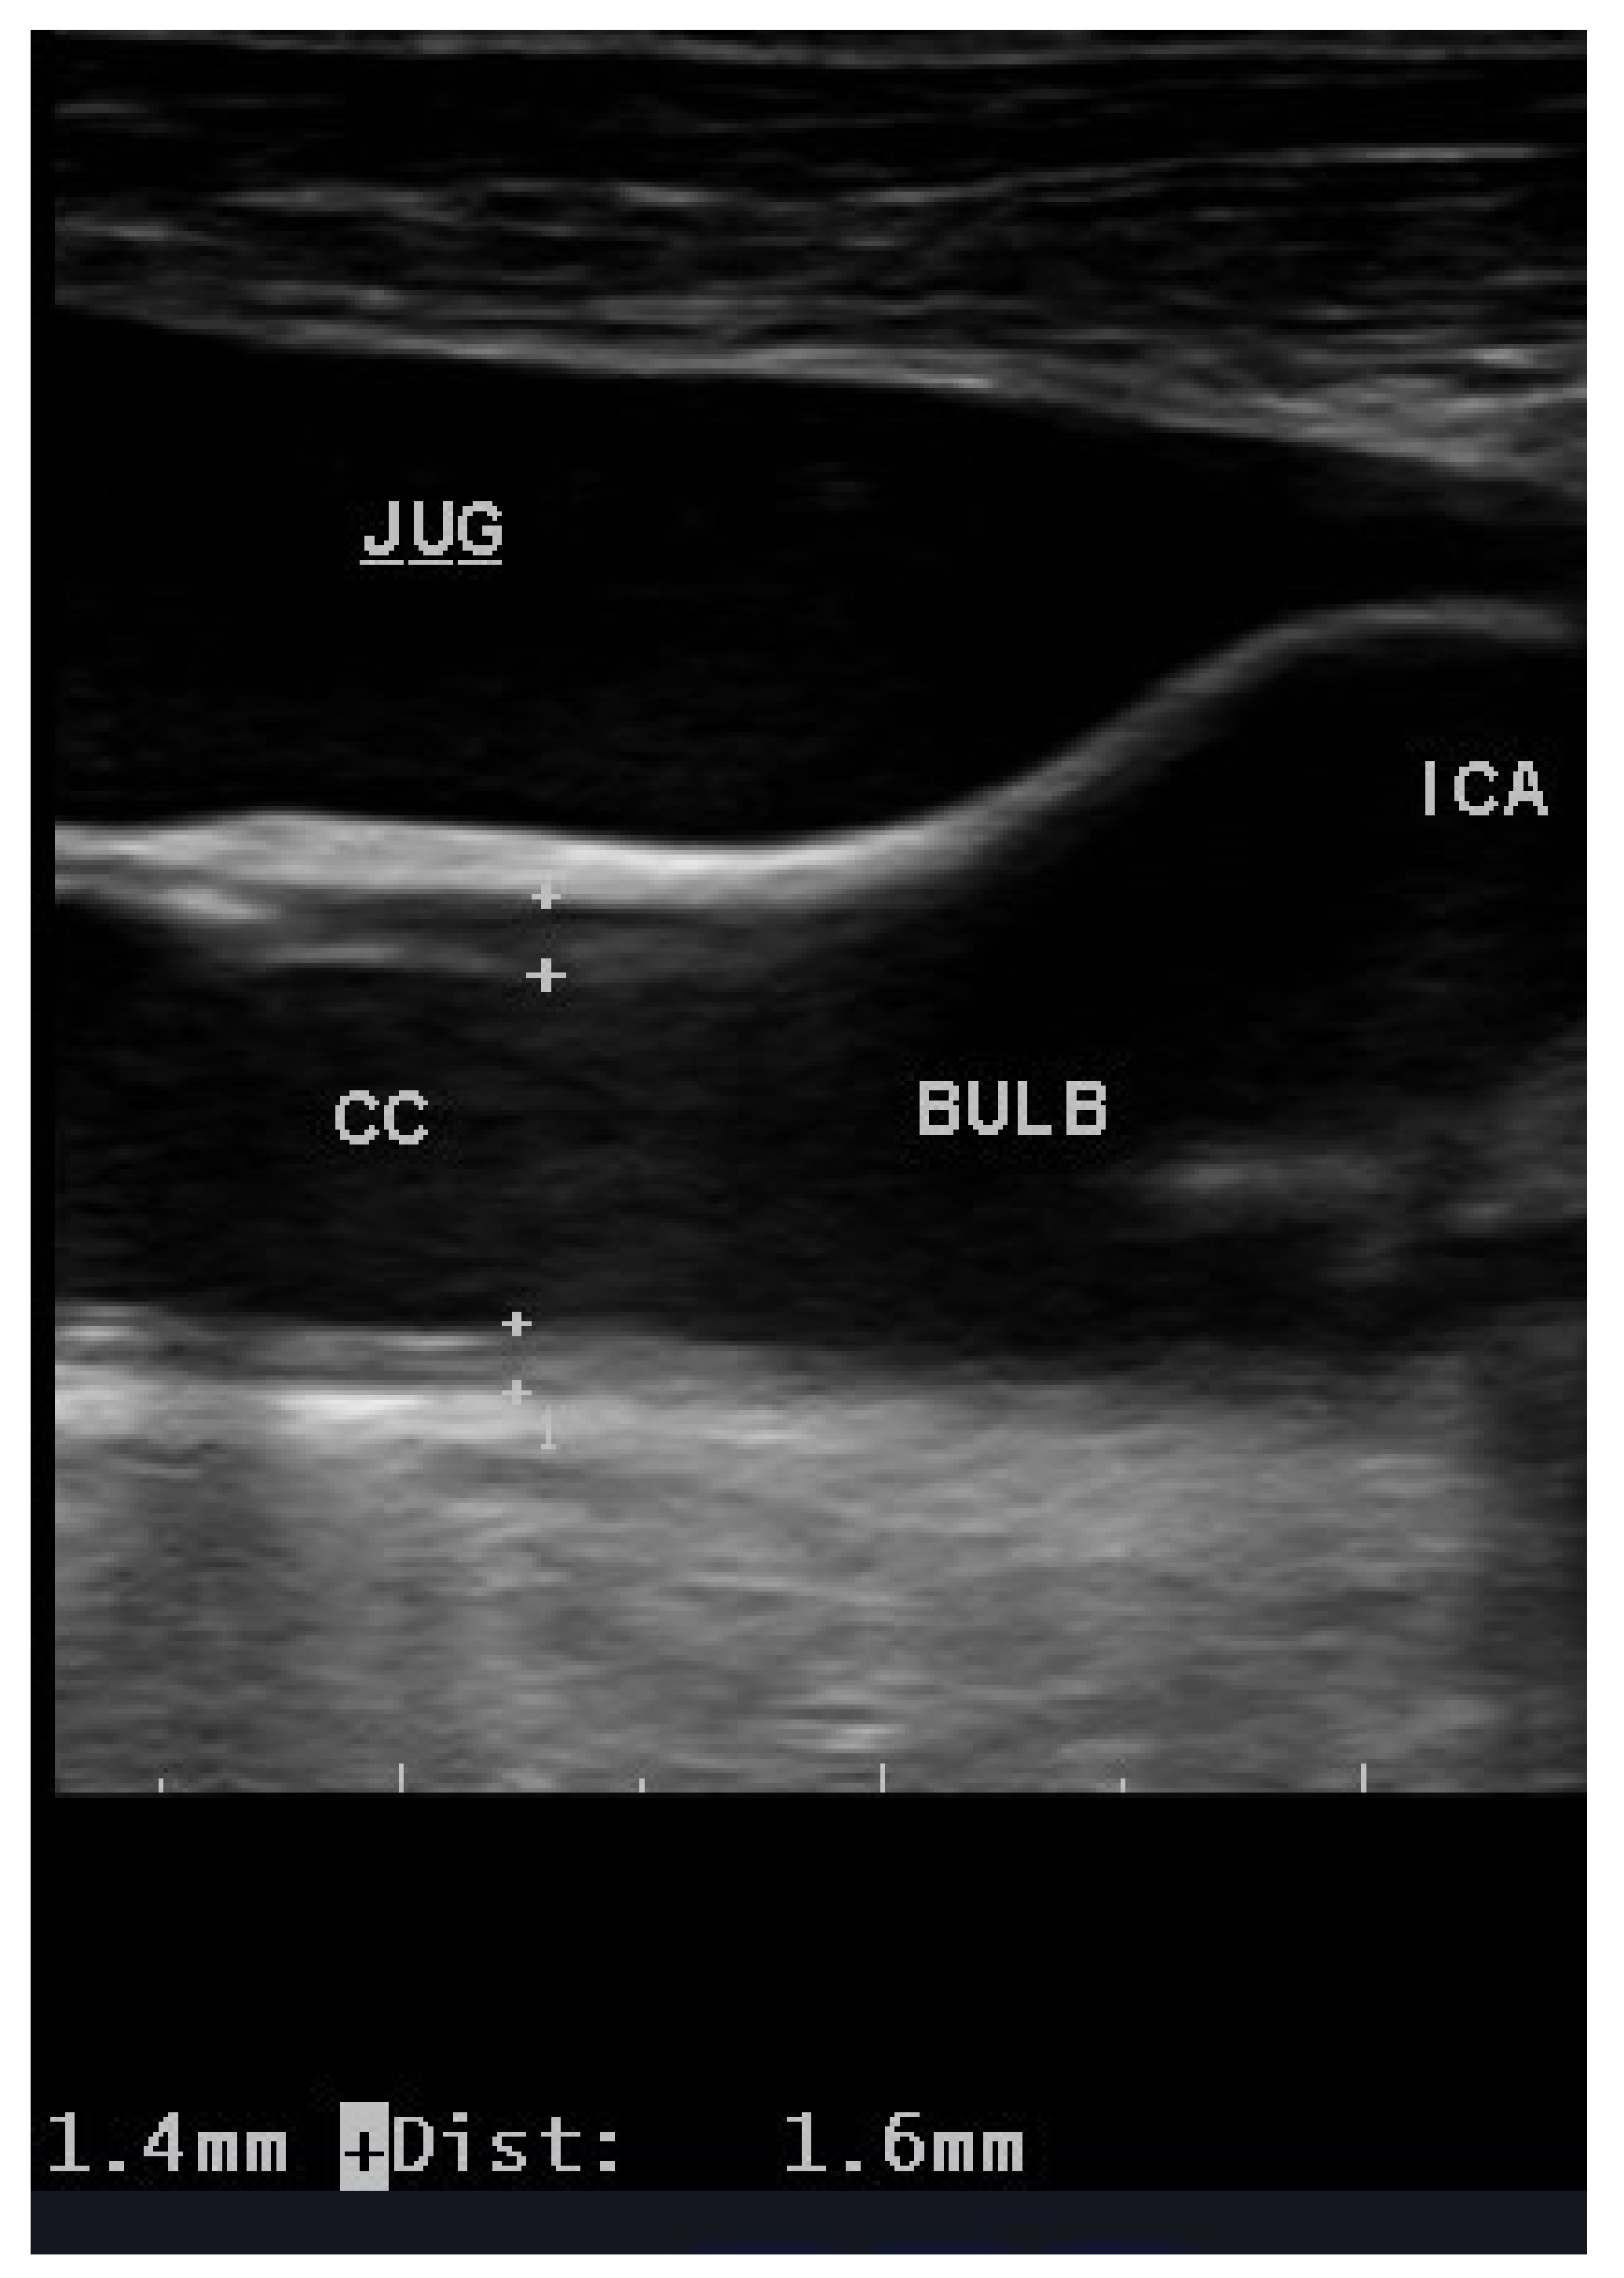

3. Carotid Ultrasound: Echography and IMT

- Pignoli, P.; Tremoli, E.; Poli, A.; Oreste, P.; Paoletti, R. Intimal plus medial thickness of the arterial wall: A direct measurement with ultrasound imaging. Circulation 1986, 74, 1399–1406. [Google Scholar] [CrossRef] [PubMed]

- Tang, R.; Hennig, M.; Bond, M.G.; Hollweck, R.; Mancia, G.; Zanchetti, A.; ELSA Investigators. Quality control of B-mode ultrasonic measurement of carotid artery intima-media thickness: The European Lacidipine Study on Atherosclerosis. J. Hypertens. 2005, 23, 1047–1054. [Google Scholar] [CrossRef] [PubMed]

- Touboul, P.J.; Hennerici, M.G.; Meairs, S.; Adams, H.; Amarenco, P.; Bornstein, N.; Csiba, L.; Desvarieux, M.; Ebrahim, S.; Hernandez Hernandez, R.; et al. Mannheim carotid intima-media thickness and plaque consensus (2004–2006–2011). An update on behalf of the advisory board of the 3rd, 4th and 5th watching the risk symposia, at the 13th, 15th and 20th European Stroke Conferences, Mannheim, Germany, 2004, Brussels, Belgium, 2006, and Hamburg, Germany, 2011. Cerebrovasc Dis. 2012, 34, 290–296. [Google Scholar]